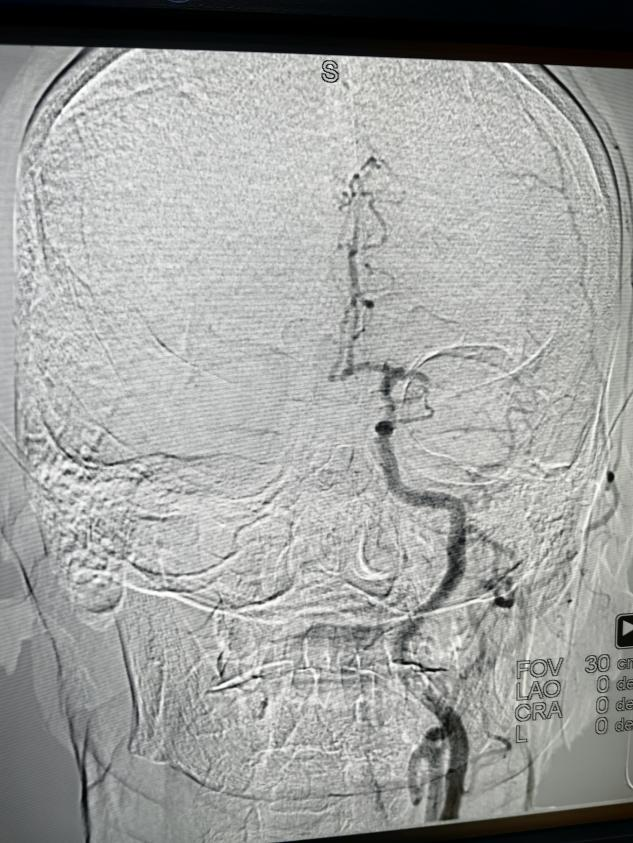

术前

术后

从接到急会诊,评估病情,谈话签字,半小时即入导管室,考虑患者年龄较大,全麻耐受能力差,麻醉风险大,给予局部麻醉。1小时内完成了穿刺股动脉建立取栓通路。造影证实左侧大脑中动脉闭塞,置入取栓器械,取出血栓血管开通。观察后再次造影,开通的血管血流恢复良好,术后 24 小时偏瘫失语基本恢复。